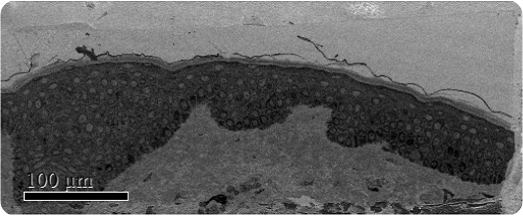

Melasma, a common dermalogical skin disease, involves the appearance of a dark skin discoloration on areas of the face upon sun exposure. The structural changes of melanocytes were studied by J.Y. Mun et al after subjecting them to Q-switched Nd:YAG laser exposure using SBFSEM (Figure 1). Melanocytes are present in the bottom epidermis layer and their dendrites can be found across all epidermis layers (Figure 2).

Figure 1. Low magnification SBFSEM image displaying the entire block-face sample with a field of view of 200 x 500μm.

SBFSEM images of the epidermis layer

Figure 2. SBFSEM images of the epidermis layer. (A) and (C) images of pre-laser treatment. (B) and (D) images of post-laser treatment. The images (A) and (B) show one section among over 500 serial sections. Arrow in (A) and (B) represent melanocytes. In (C) and (D), dark green represents melanocytes and light blue show nucleus. Yellow, purple, red and cyan dots show melanosomes. The images (C) and (D) show a decrease of the volume of melanocyte and the number of melanosome after laser treatment. Size bar is 2μm.